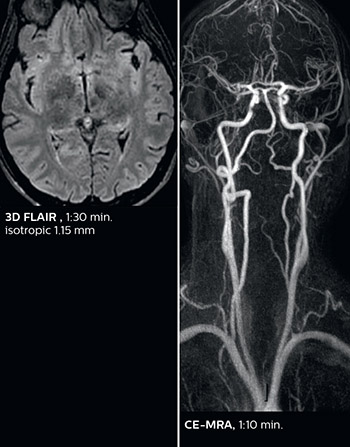

“We used to have long examination times for certain types of patients, a few lasting more than 40 minutes,” says Dr. Savatovsky. “What is remarkable, is that now all these examinations are below 30 minutes, which opens up opportunity to add more sequences when needed. It’s really hard to keep a patient for more than 40 minutes in the scanner, but because we have now cut scan times by at least 10 minutes, we can add more sequences without making the exam too long. And this is where the new system helps us make a difference. Examples include our examinations for informing brain tumor classification or giant cell arteritis workup, or for intracranial wall imaging – so in patients where we need several advanced sequences or high resolution sequences.” “We added three additional sequences in our brain neoplasm classification exam: a 3D SWI sequence, APT and ASL on top of 3D morphologic sequences, an isotropic DSC (dynamic susceptibility contrast) and multivoxel spectroscopy. I think that in patients that need a classification for brain mass, for example, we can provide a more detailed and confident diagnosis than before, allowing the clinicians to decide for either a medical workup if no tumor is suspected, or for neurosurgery as soon as possible if a neoplasm is suspected.” “In multiple sclerosis patients, we increasingly include a multishot susceptibility sequence [3] in our routine cases, thanks to the shorter scan times. Our abbreviated MS protocol for brain is around 8 to 9 minutes, so we can ask for one or two additional sequences to visualize the central veins, or to get an additional contrast to better depict posterior fossa lesions. In cases of white matter lesions of unknown significance on FLAIR images, for example when we see high signal hyperintensities in the brain, we can add on more advanced sequences such as PSIR (phase sensitive inversion recovery) or susceptibility-weighted sequences to help us in distinguishing between MS and nonspecific or vascular abnormalities in these inflammatory cases.”

Dr. Savatovsky appreciates the improvements and flexibility that Elition with Compressed SENSE and MultiBand SENSE provides, particularly for stroke patients. “For stroke, it allows us to cut about 5 minutes off of our stroke protocol, or to keep the same acquisition time and get more insights.” The ability to perform more sequences can help in making a swift and confident diagnosis. “For example, our stroke cases usually include the regular sequences that every center does (b1000 diffusion, FLAIR, time-of-flight angiography), but we also image supra aortic vessels, and we can replace a gradient echo sequence with a fast 50-second susceptibility-weighted sequence, and all of this doesn’t add much time. because all the regular sequences are accelerated on Elition.” “The time savings with Compressed SENSE and MultiBand SENSE make it easier to add sequences to give us additional insights. Depending on the context and the first results, we might add a DSC perfusion to assess the ischemic penumbra, an ASL perfusion to help find an alternative cause in case of normal diffusion, or add a high-resolution T1 sequence for a stroke patient, to quickly assess wall imaging in emergency cases. The additional sequences can help improve patient management, because we can already consider some alternative diagnoses if the morphological MRI is normal.”

In this patient with acute right motor deficit and aphasia, the b2000 diffusion weighted image is normal. The SWIp image demonstrates more prominent veins in the right hemisphere, which could reflect increased deoxyhemoglobin contents. Fast ASL shows low CBF regions in the left frontal lobe. A follow-up ASL after one hour demonstrates high CBF values in the same area. The final diagnosis was migraine with aura.